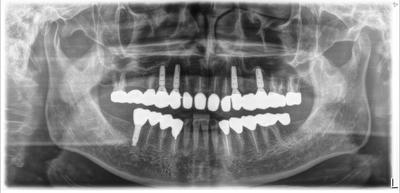

術後5年。

前医により無理な設計、精度の低いブリッジが装着せれていたが、動揺強くなり当院受診。

欠損部をブリッジではなく、インプラントにて咬合機能回復。

使用インプラントは上顎=アストラテック(スウェーデン)、下顎=Biomet 3i(アメリカ)。

本ケース、Biomet 3iにはプラットホームシフトは行っていないので、インプラントシューティングサーフェイス周の囲骨違いがよく分かる。

一部ソケットリフトによる骨移植を行っている。

右下7部にインプラント治療行っていないのはコスト低減のため。

当然、インプラント以外の様々な治療分野を総動員しての包括診療=フルハウスリコンストラクションケース。

強度の歯ぎしりがあるため、ナイトガードはマスト。